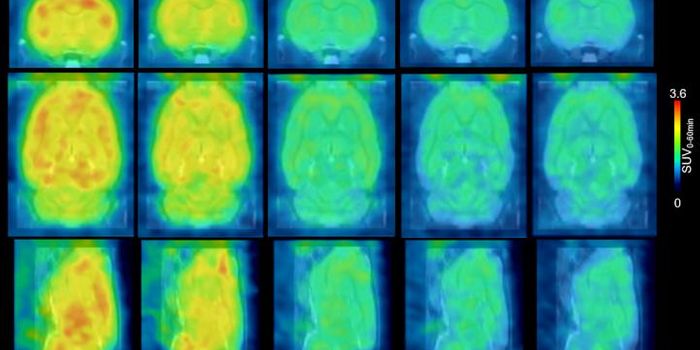

MAY 05, 2020Clinical & Molecular DXImagine a future where we could “see” inside the human brain at stunning high resolution, detecting the earl ...

JUN 27, 2019Chemistry & PhysicsFor positron emission tomography (PET) scans, patients are injected with a radioactive probe that emits positrons (a pos ...